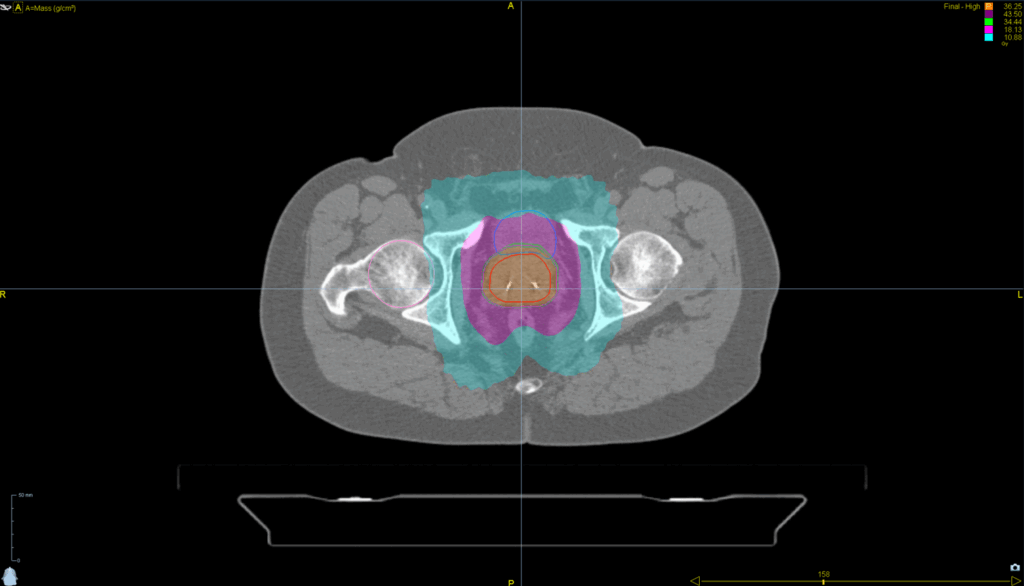

Treatment Plan Images

Fractionation / Protocol Used

36.2 Gy in 5 fractions

PTV(s) Volume

6 cm, 117 cc